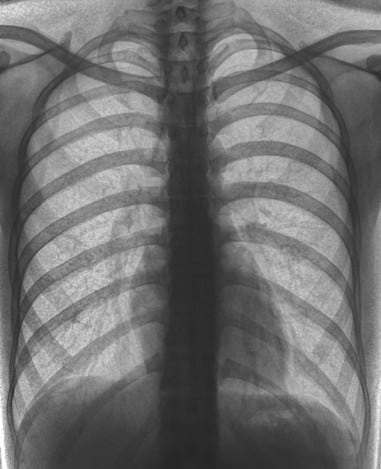

rib fractures and skeletal trauma

Rib and Skeletal Trauma

Lung Injury and Pulmonary Abnormalities